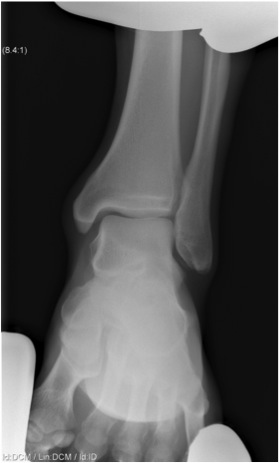

Xray

Associated fractures

- Weber C

- Maisonneuve

| Increased tibio-fibular Clear space | Overlap | Increased medial clear space |

Medial border of the fibula Lateral border of the posterior tibia (incisura fibularis) Measured 1 cm above the plafond |

Overlap of the fibula and the anterior tibial tubercle | Deltoid ligament injury |

| <5mm AP and mortise |

> 6 mm AP view > 1 mm mortise view |

Maisonneuve / proximal fibular injury |

Lack of overlap and increased clear space on right

Clear isolated disruption to the syndesmosis